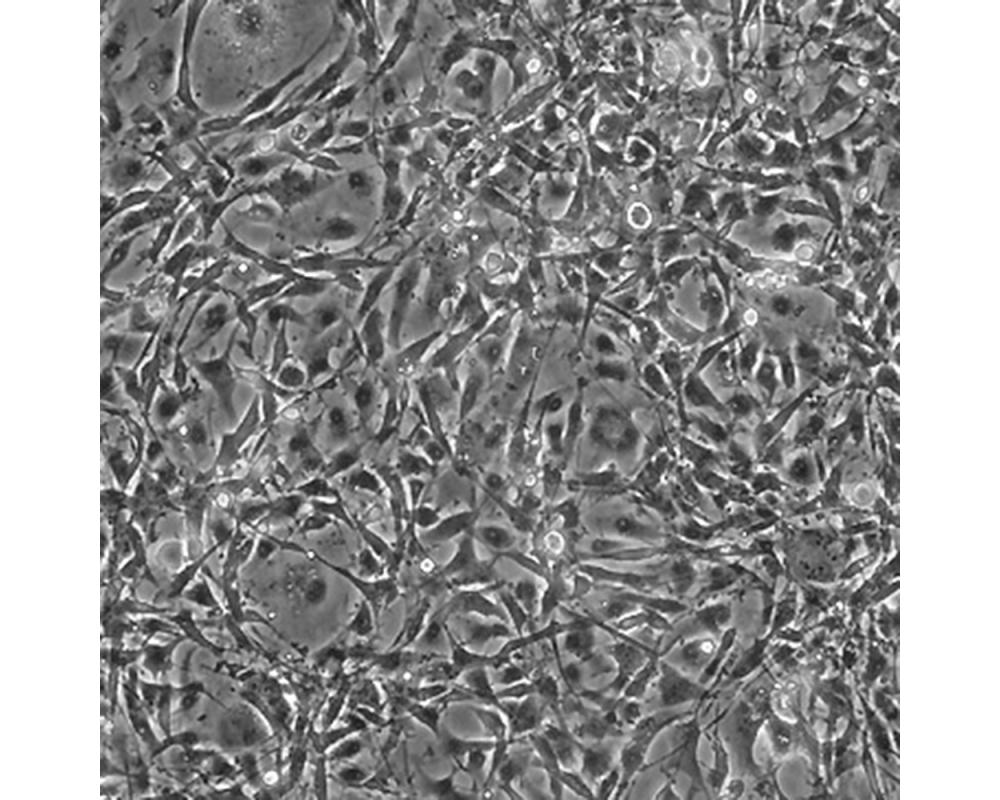

U-118 MG

產(chǎn)品名稱 U-118 MG

中文名稱 人腦星形膠質(zhì)母細胞瘤

組織來源 星形膠質(zhì)母細胞瘤;男性

細胞種屬 Homo sapiens, human

生長特性 adherent

培養(yǎng)基 DMEM+10% FBS+1% P/S

形態(tài)特征 mixed

細胞描述 注意: 據(jù)報道來自不同個體的膠質(zhì)母細胞瘤細胞株U-118 MG (HTB-15) 和 U-138 MG (HTB-16)有著一致的VNTR和相近的STR模式。 U-118 MG 和 U-138 MG細胞遺傳學上很相似并有至少六個衍生標記染色體。 這是1966年至1969年間J. Ponten和同事從惡性神經(jīng)膠質(zhì)瘤中構(gòu)建的細胞株中的一株(其它包括ATCC HTB-14和 ATCC HTB-16 and ATCC HTB-17)。 1987年用BM-Cycline培養(yǎng)6周去除了支原體污染。